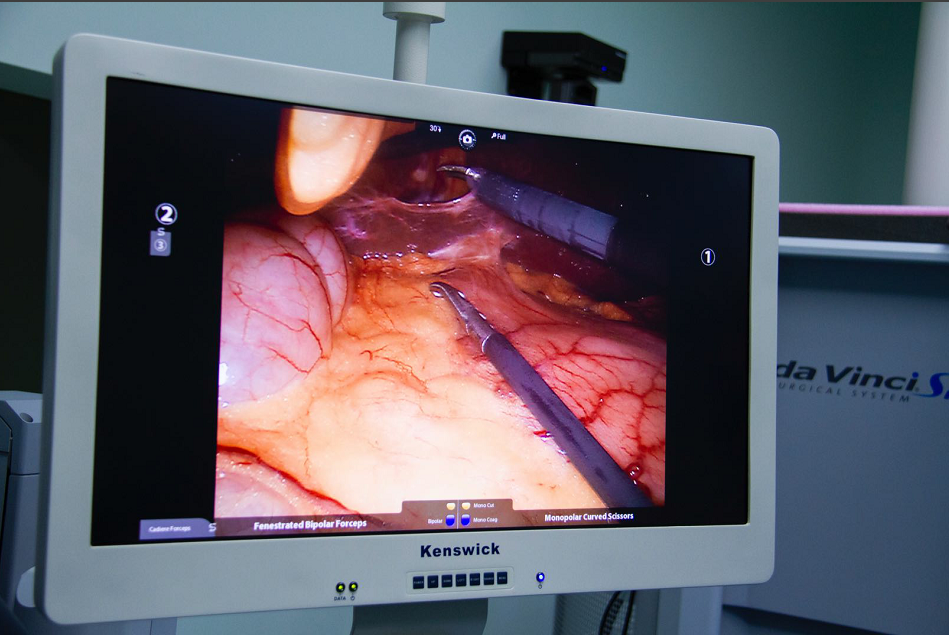

达芬奇手术机器人给患者手术中

达芬奇手术机器人的全称是内窥镜手术器械控制系统(英文名da Vnici S),它与腹腔镜系统相结合,主刀外科医师在远离手术台的操作控制台,用手遥控着装配在手术台上的4个机械臂,控制连接在机械臂上的腹腔镜和手术器械的动作和运转,完成各类手术。可以说达芬奇手术机器人的出现,将外科医师从手术台上解放了出来。

1、机器人的摄像系统为外科医师提供了更清晰和逼真的三维视野,机器人的“眼睛”高清立体,手术视野放大10倍,细小的组织也难逃火眼金睛;

光学放大10倍的高清晰立体图像